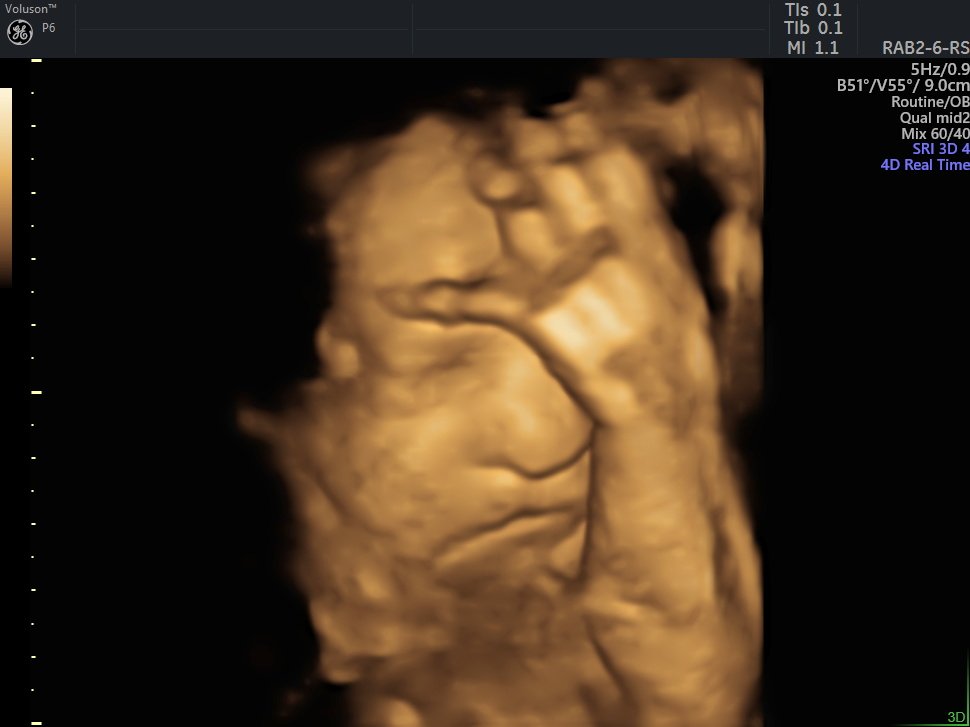

4 D Ultrasonografi

4 Boyutlu (Renkli) Ultrason ve Doppler Ultrasonografi